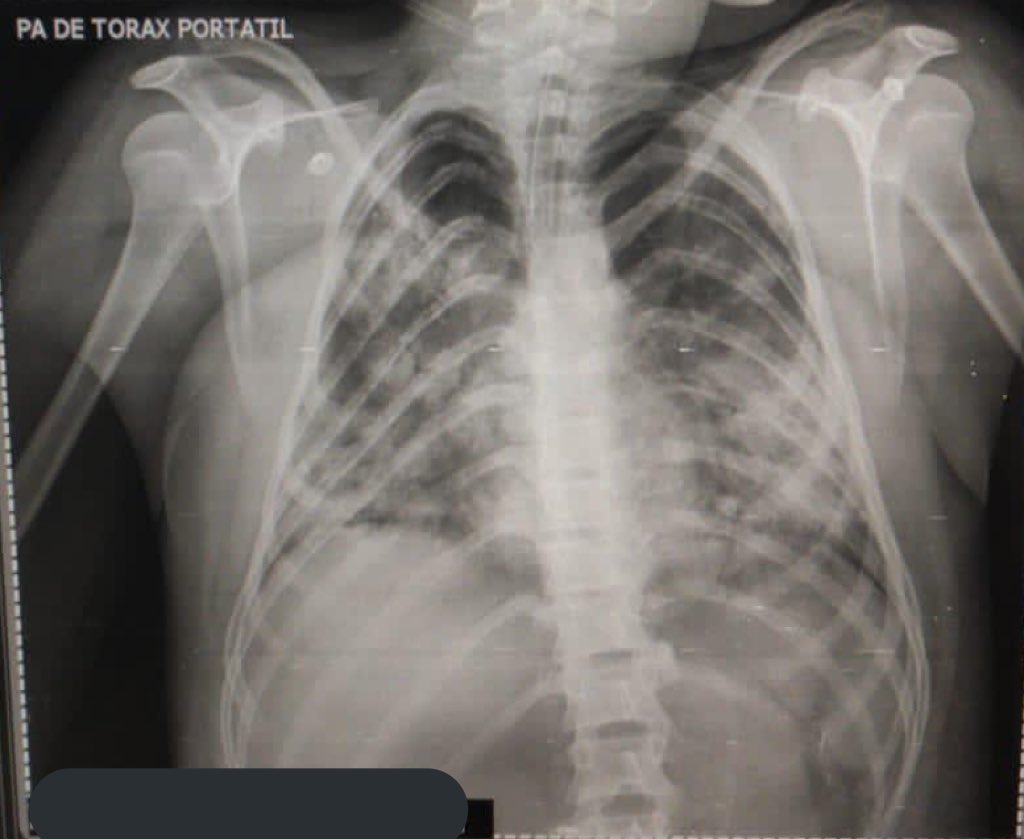

Adolescente de 13 años de edad, contagiado de COVID-19. Otra razón para evitar el regreso a clases presenciales, no es momento y aquí está la prueba. Vean el daño tan severo en sus pulmones 👇🏻

Vean el daño tan severo en sus pulmones 👇🏻